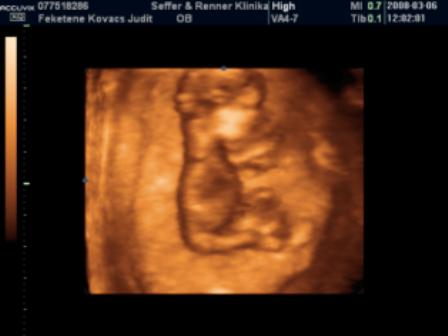

Mi holnap este megyünk.Ilyenkor még végigjárjuk a nagyszülőket + egy kis vásárolgatás, este 9-től hamarabb nem hiszem, hogy hazaérünk, de jövök majd a beszámolóval és a fotóval.